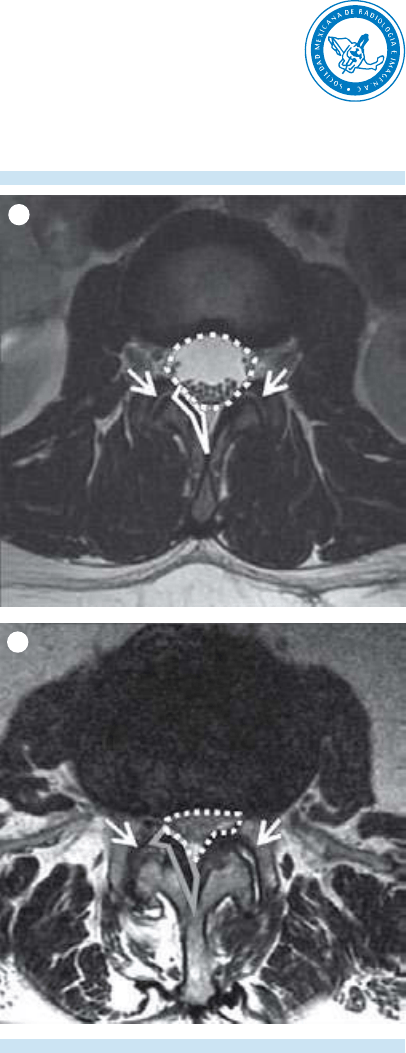

5. Evaluación de las 3 “c”: cordón espinal,

cono medular y cauda equina.